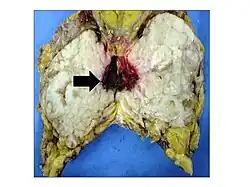

Phyllodes tumors may be considered benign, borderline, or malignant depending upon their histological features, including stromal cellularity, infiltration of the epithelial-stromal interface, and mitotic activity.[15] Due to their propensity to metastasize and grow quickly, almost all phyllodes tumors are regarded as having malignant potential and treated accordingly.[15] A large case series from the MD Anderson Cancer Center reported the incidence of each type of phyllodes tumor as benign (58%), borderline (12%), and malignant (30%).[16]

Malignant phyllodes tumors can behave similarly to sarcomas leading to development of blood-borne metastases.[16] Approximately 10% of phyllodes tumor develop distant metastases and this occurrence is higher (20%) in patients with histological-identified malignant tumors.[16] The most common site for distant metastases include the lung, bone, and abdominal viscera.[17] In more insidious cases, the parotid region has also been described in literature.[18]